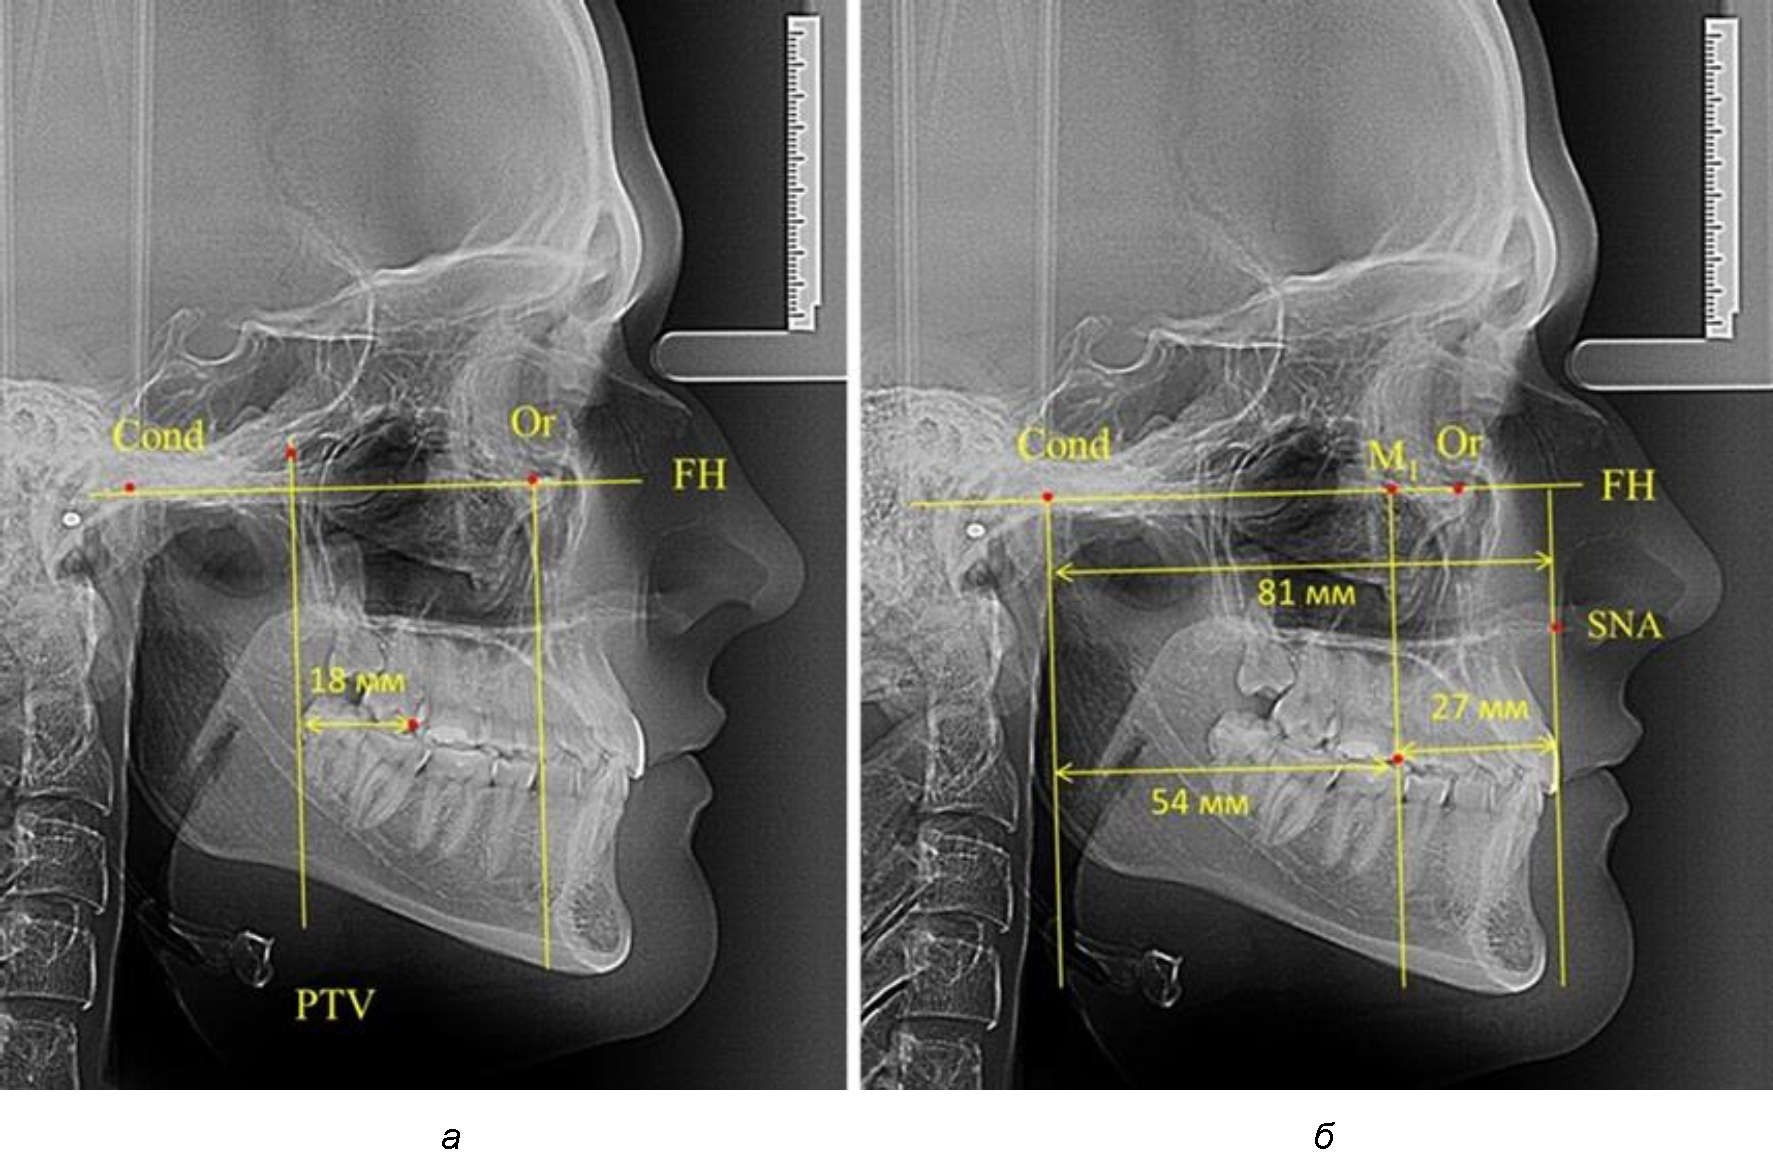

При проведении анализа к Франкфуртской горизонтали проводили передний и задний перпендикуляры. Передний спинальный перпендикуляр проходил через выступающую точку передней носовой ости (spina nasalis anterior – SNA), а задний суставной перпендикуляр опускали из кондилярной точки Cond. Молярный перпендикуляр проводили через медиальную поверхность первого постоянного моляра. Указанная вертикаль отделяла замещающие зубы постоянного прикуса от добавочных зубов (постоянных моляров), что вполне логично для анализа положения первых постоянных моляров в гнатическом комплексе (рис. 1).

Рис. 1. Метод определения положения первых верхних моляров по Ralph E. McDonald (а) и по предложенному методу (б)

Так, при расстоянии от крыловидной вертикальной плоскости PTV до дистальной поверхности верхнего первого постоянного моляра в 13 мм сагиттальный размер гнатического отдела был 82 мм. При этом отношение кондилярно-спинального расстояния к кондилярно-молярному размеру (54,5) было близким к коэффициенту 1,5, что представлено на рис. 2.

В то же время при увеличенном расстоянии от крыловидной вертикальной плоскости PTV до дистальной поверхности верхнего первого постоянного моляра, равное 23 мм, сагиттальный размер гнатического отдела составил 92 мм. При этом отношение кондилярно-спинального расстояния к кондилярно-молярному размеру (30,5), так же, как и при малых размерах, было близким к коэффициенту 1,5, что представлено на рис. 3.